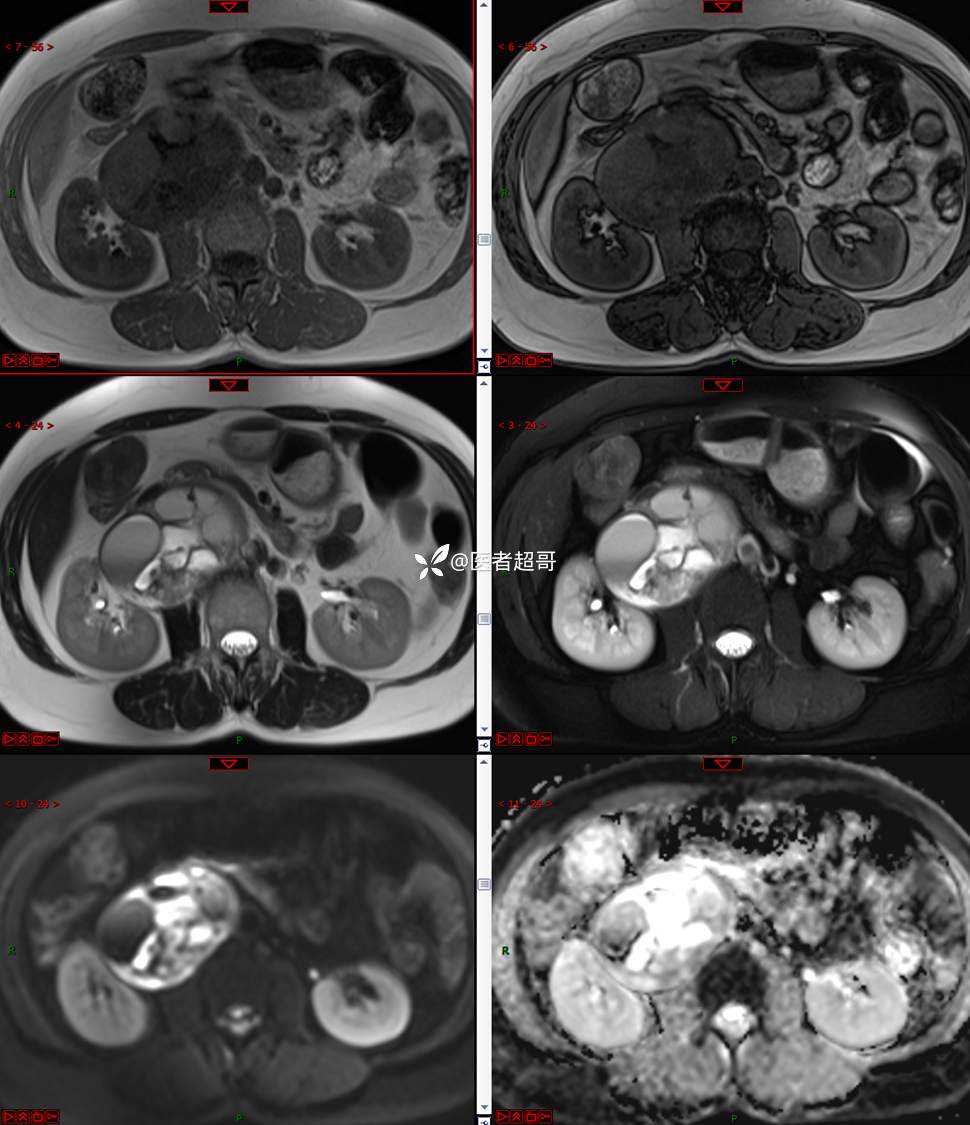

【影诊笔记671】定位有难度,究竟是腹腔内or腹膜后,请先定位,再定性!有结果~~~

hyy838 推荐女,52岁

主诉:查体发现腹部肿物1周。

现病史:患者1周前于我院查体发现右侧腹部肿物,无腹痛、腹泻、便血,无恶心、呕吐,患者为求进一步治疗,遂就诊于我院,门诊以“腹部肿物”收入院。患者自患病以来睡眠可,精神可,饮食可,小便无明显异常,体重无明显变化。

专科检查:腹部平坦,腹肌软,无压痛及反跳痛,无包块,肝脾无肿大,Murphy征阴性,腹部叩鼓,肝脾双肾无叩痛,移动性浊音阴性,肠鸣音正常。我院 肝胆胰脾肾彩超提示:脂肪肝、腹腔内囊实性团块,建议进一步检查。